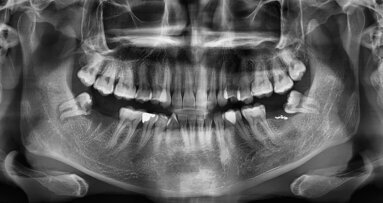

GOTHENBURG, Sweden: Older age is a major predictor of various health issues, including cognitive and cardiovascular disease, hearing loss and progressive skeletal deformation. Research has also linked older age with height loss, which is associated with increased morbidity and mortality. As the mandibular bone contains ample information about the general bone condition, a recent study has demonstrated that information on mandibular bone structure gained from radiographs during routine dental check-ups may help predict future height loss, thus paving the way for timely prevention.

In the study, the researchers employed data on 937 Swedish women born between 1914 and 1930 (middle-aged and elderly at baseline), drawn from the Prospective Population Study of Women in Gothenburg. They assessed their mandibular cortical erosion and trabecular sparseness and calculated their height loss over three periods: 1968–80, 1980–92 and 1992–2005. Each participant had undergone health and dental check-ups at least twice during the monitoring period.

The study reported that the participants annually lost 0.075 cm, 0.08 cm and 0.18 cm, respectively, over the three observation intervals. This resulted in 0.9 cm, 1.0 cm and 2.4 cm in total for all three periods. The study also demonstrated that the percentage of women with severe cortical erosion rose from 3.2% in 1968–80 to 11.1% in 1980–92 and up to 49.8% in 1992–2005. Similarly, the prevalence of sparse trabeculation increased from 20.6% in 1968–80 to 33.5% in 1980–92 and up to 41.6% in 1992–2005. In each period, height loss was greatest in those with severe cortical erosion and those with sparse trabeculation and significantly predicted height loss over the next 12–13 years.

The researchers acknowledge that the study is observational and has some limitations. Therefore, no firm conclusions can be drawn yet. However, they noted that the structural bone changes seen in the jawbones of the study participants resemble those of the vertebrae, which could explain height reduction. “[These changes] may therefore serve as proxy indicators when screening in the early phases of bone degenerative pathogenesis, signalling the ongoing bone remodelling and the need for further clinical attention to older women at risk of height loss,” the authors noted.